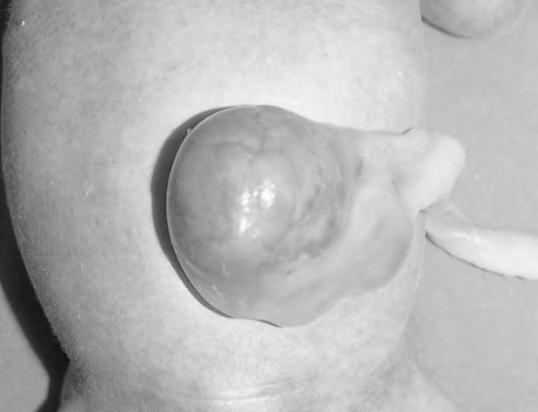

Hernia umbilical

La cicatriz umbilical se refuerza en el plano musculoaponeurótico por la fibrosis del uraco, vena umbilical, arterias umbilicales y por la extensión de la fascia de Richet, que se prolonga desde la fascia transversalis. Cuando la resistencia fascial resulta insuficiente y se combina con aumento de la presión abdominal aparece una hernia umbilical. Se presenta con frecuencia en los primeros días de vida por la salida de asas intestinales o epiplón a través del anillo umbilical. Se manifiesta como una tumoración que propulsa a nivel del ombligo que aparece evertido (Fig. 2.30.1). Es fácilmente reductible, palpándose entonces un orificio herniario rodeado de bordes duros (anillo umbilical). Debe ser diferenciada del ombligo cutáneo, simple eversión de la piel umbilical sin la presencia de hernia. La incidencia a los pocos días del nacimiento es superior en la raza negra (30%) respecto a la blanca (4%). Al año de vida las cifras se reducen a menos de la mitad, demostrando la tendencia espontánea hacia la curación. La frecuencia es muy alta en prematuros (75% en menos de 1.500 g), síndrome de Down, hipotiroidismo, síndrome de Hurler y en las trisomías 13 y 18. En algunos casos de síndrome de Beckwith-Wiedemann una gran hernia umbilical sustituiría al onfalocele.